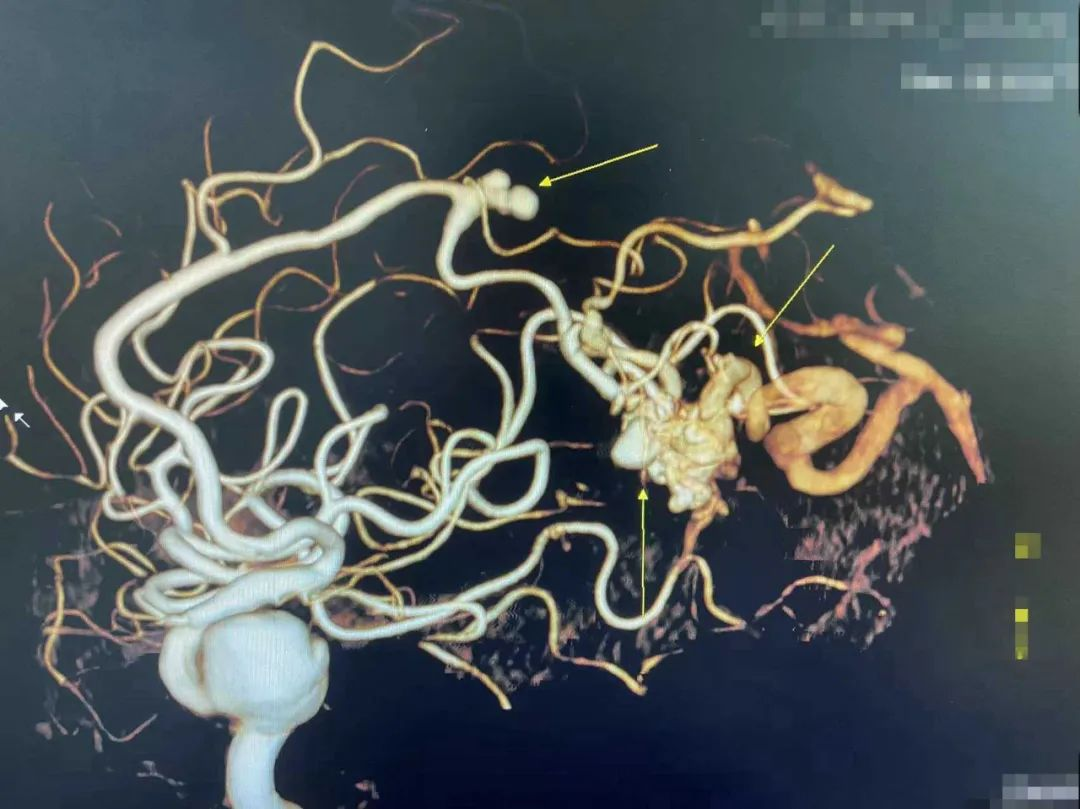

▲箭头为颅内动脉瘤及动静脉畸形

我院副院长、神经外科学科带头人王鹏,神经外科客座教授陈光忠,介入手术团队联合进行术前讨论认为:患者多发动脉瘤,右侧颈内动脉海绵窦段动脉瘤巨大,右侧大脑前动脉瘤A4段动脉瘤载瘤动脉与右侧枕顶叶交界区动静脉畸形主要供血动脉密切相关,出血责任血管为:右侧枕顶叶交界区动静脉畸形,建议进一步完善脑血管造影(DSA)辨别。

全脑血管造影提示大脑前动脉为主要供血动脉,大脑后动脉参与供血(同时可见动脉瘤及动静脉畸形),大脑前动脉A4动脉瘤瘤体不规则、但瘤壁尚平滑,非破裂形态;远端动静脉畸形为大脑前动脉、大脑中动脉、大脑后动脉分支等多支血管供血,巢里可见动脉瘤样改变,瘤顶突出,考虑为出血病灶。